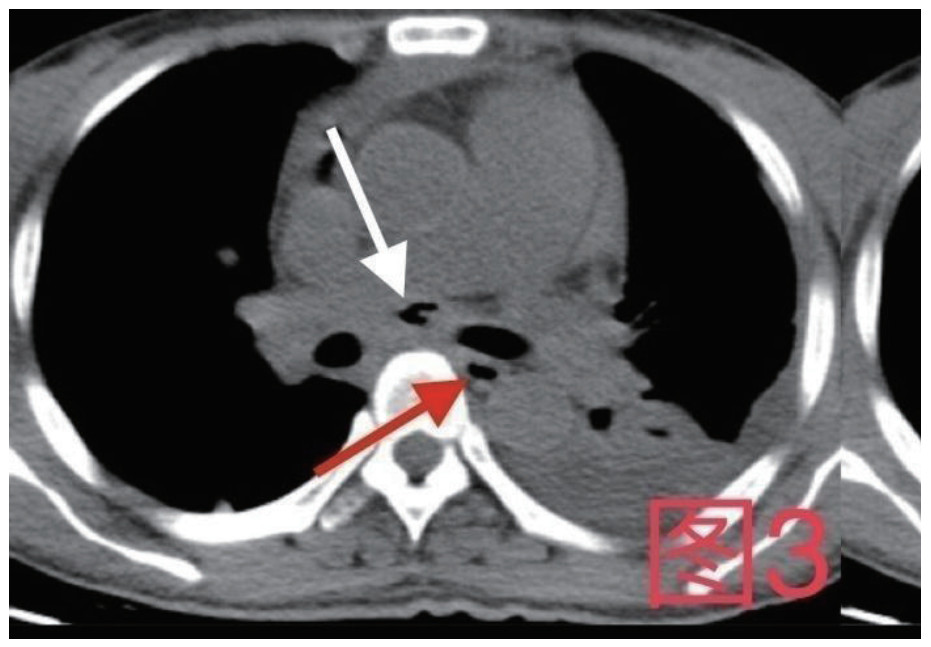

治疗经过:急诊予美罗培南0.5 g,1次/12 h抗感染,补液支持,心包引流等治疗措施,收住感染科后继续抗感染治疗,期间心包积液培养出白假丝酵母菌,加用氟康唑200 mg,1次/d, 口服,心包积液、左侧胸腔积液引流等措施,治疗10 d后复查胸部CT仍有中大量心包积液伴少许积气,纵隔积气;左侧少量胸腔积液,两肺叶间裂少许积液。对照前片(2020.10.26)心包积气及左侧胸前积液有增多,叶间裂积液新发,心包积液略有减少。右肺下叶感染,左肺下叶膨胀不全,较前右肺下叶感染有吸收,左肺下叶膨胀不全新发。考虑不能排除食管纵隔瘘,予口服碘海醇后胸部CT检查(图 3~6):约胸6椎体水平食管纵隔瘘,瘘口为相应水平食管壁右前方可能;胃镜(图 7):食道距门齿25 cm右后壁见一直径约1.0 cm凹陷,内有一小瘘口。胃镜下予钛夹2枚夹闭瘘口(图 8),同时植入空肠营养管。至此患者病情明确诊断食管心包瘘,患者经以上治疗后心包积液、胸腔积液逐渐减少,于11月13日拔除心包及胸腔引流管,因患者签字回当地就诊,予口服莫西沙星、氟康唑带药出院,出院后随访,患者未回当地医院治疗,仅在家中继续空肠营养管饲喂及口服抗菌药物治疗。

| 图 3 白色箭头所指为气管隆突下方纵隔内积气,红色箭头所指为食管 |